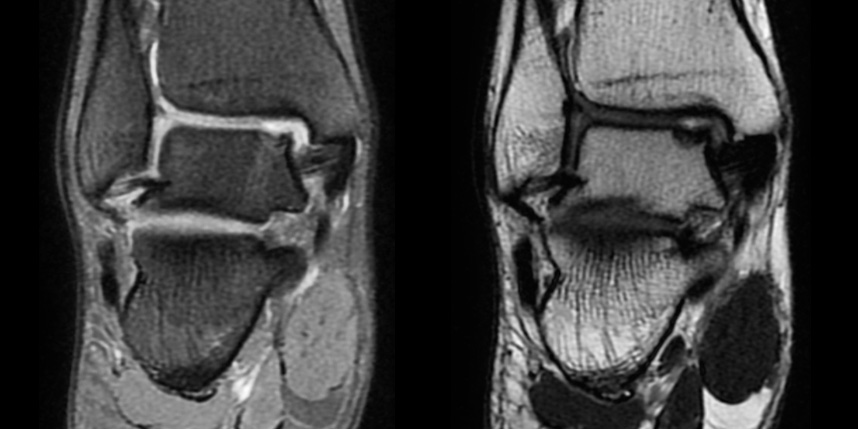

연골재생술 진행

(미세천공술 + alpha)

타병원 미세천공술 실패 후 통증으로 내원하신 사례

* 환자에게 받은 소중한 자료입니다.